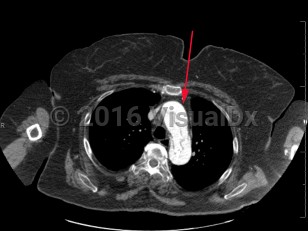

Aortic dissection is an intramural tear of the aorta. Aortic dissection is a life-threatening emergency. Tears often occur in the intimal layer of the aorta, with blood collecting in the medial layer. Back pain is the common presenting symptom, but it may also present with chest pain, dyspnea, or a new neurologic deficit. Syncope and hypotension occur less frequently. Aortic dissections most often occur in older men.

- Type A – dissection involving ascending aorta

- Type B – dissection that does not involve ascending aorta (ie, aortic arch and descending aorta)

- DeBakey I – ascending and descending

- DeBakey II – ascending only

- DeBakey III – descending only